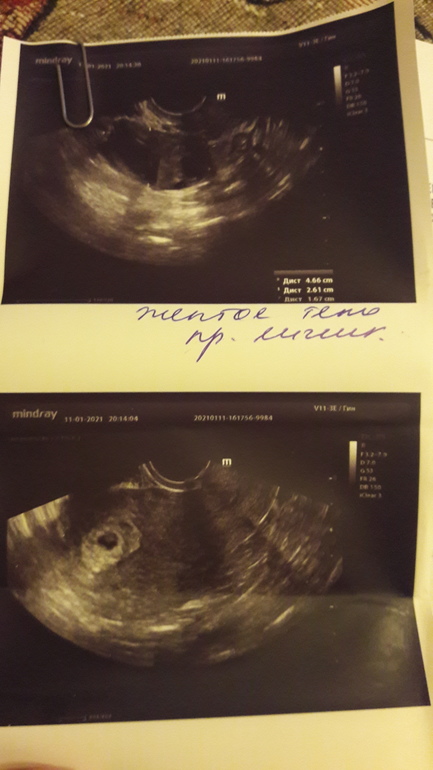

6+2 узи

Анализы и процедуры. Помощь в расшифровке результатовДобрый вечер. Сегодня наконец была на узи. Думала сердечко уже будет не просто сб+, но нет Г сказала рано (может от аппарата зависит) смотрю многим уже писали ЧСС...Уже дома увидела: хорион- выше внутреннего зева. Это что значит?

И еще как я и думала есть полноценное ЖТ

не пойму что она ручкой подписала?

"Жёлтое тело правый яичник" написано